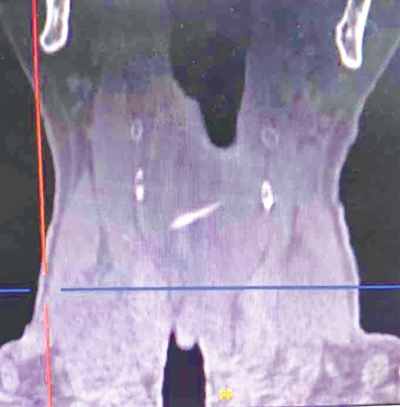

原来,王老太吃晚饭时不小心被鱼刺卡住,家人赶忙带她去当地医院就诊,医生仔细检查后却未能发现鱼刺的踪迹。随后,家人又带着老人前往另一家医院,CT检查显示鱼刺位置较深,医生建议通过胃镜取出。然而,医生操作着胃镜看到鱼刺准备抓取的关键时刻,老人活动了一下,鱼刺竟然不见了踪影,首次取刺行动以失败告终。第二天,经朋友介绍,老人和家人来到城阳区人民医院耳鼻喉科,医生接诊后通过影像学检查发现鱼刺位置比较深,并且鱼刺是从右下斜向左上刺入的,这种情况特别棘手,内镜下很难取出。一旦无法取出,可能需要做颈侧切开来寻找异物。耳鼻喉科医生对影像片子进行仔细分析后,决定在全麻食道镜下进行探查。完善各项术前准备后,麻醉医生成功而快速地让老人进入了理想的麻醉状态,耳鼻喉科团队从左侧梨状窝进食管镜,缓慢向右侧梨状窝移动,避免鱼刺进一步深入组织里,很快就找到了鱼刺的一端,然后再用钳子夹住看到的一端,先向食道方向走行,等把鱼刺完全从组织取出后再通过食道镜完整取出。城阳区人民医院耳鼻喉科副主任杨栋介绍,整个手术过程虽然紧张但很顺利,仅用了3分钟就成功将那根“顽皮”的鱼刺取出。